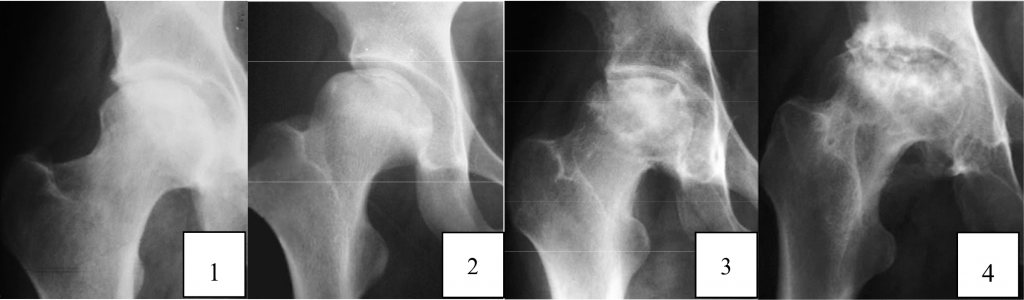

แพทย์จะวินิจฉัยจากประวัติ การตรวจร่างกาย และการใช้ภาพเอกซเรย์ร่วมกัน บางครั้งอาจจําเป็นต้อง ใช้ภาพเอกซเรย์คลื่นแม่เหล็กไฟฟ้าร่วมด้วย เพราะในระยะแรกของโรค อาจไม่พบความผิดปกติจากภาพเอกซเรย์ ชนิดธรรมดา

คือภาวะที่เซลล์กระดูกในหัวสะโพกตายจากสาเหตุต่างๆ ส่วนใหญ่เกิดจากการขาดเลือดไปเลี้ยงกระดูก หัวสะโพก ทําให้ความแข็งแรงของกระดูกลดลง เกิดการยุบตัวของกระดูกหัวสะโพกตามมา หากไม่ได้รับการ รักษา โรคจะดําเนินไปเรื่อย ๆ จนเกิดภาวะข้อสะโพกเสื่อมตามมา และเป็นสาเหตุสําคัญอันดับแรกที่ต้องผ่าตัด เปลี่ยนข้อสะโพกเทียมในโรงพยาบาลมหาราชนครเชียงใหม่